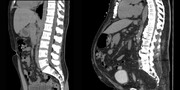

جراحی چاقی برای کدام گروه سنی مناسب نیست؟

به گفته دانشیار دانشگاه علوم پزشکی ایران، چاقی مرضی امروز دیگر صرفاً یک مسئله ظاهری نیست، بلکه بهعنوان یک بیماری مزمن با پیامدهای جدی جسمی، روانی و اجتماعی شناخته میشود.